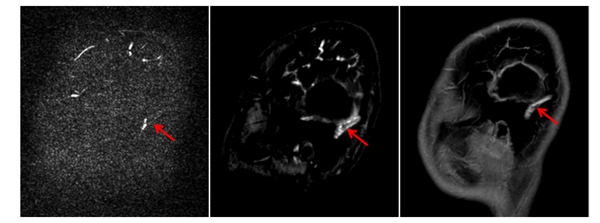

▲对比检查显示,CE-MRV(中间图)较常规PC-MRV(左图)能更准确显示乙状静脉窦内血栓的位置和范围,为临床治疗提供了可靠依据,患儿经过十天对症治疗后复查显示同一部位血栓明显缩小(右图)。

在儿科团队的全程监护下,小卓顺利完成对比增强磁共振静脉成像(CE-MRV)检查。放射影像科团队通过优化扫描方案和动态监测造影剂循环时相,成功获取了高质量的诊断影像,清晰显示了颅内静脉窦血栓的具体位置及累及范围。基于这一精准的影像学评估,儿科治疗团队为小卓制定了个体化综合治疗方案,最终头痛等症状明显改善,后续影像复查证实血栓范围明显缩小,治疗效果达到预期目标。